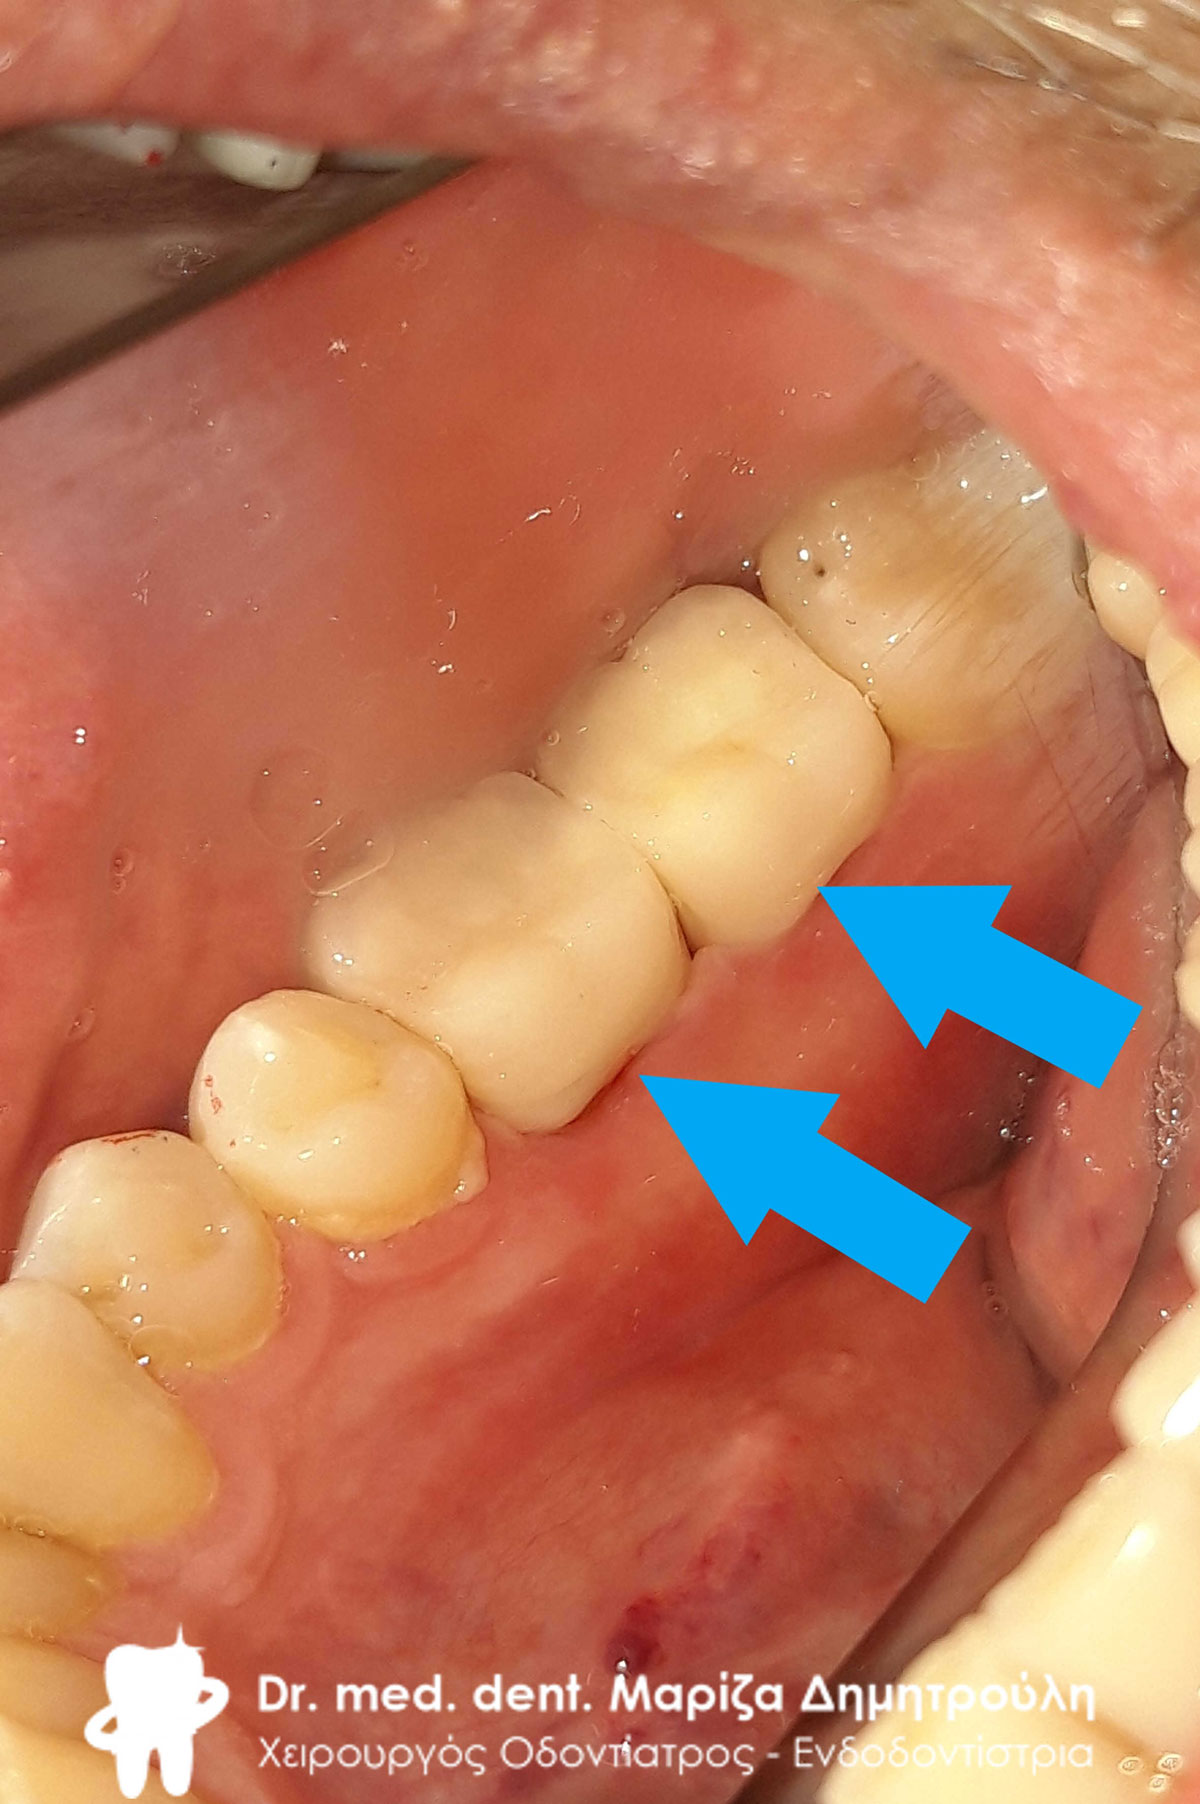

Περιστατικό – Ολοκεραμικό επένθετο ζιρκονίου στον άνω αριστερό γομφίο

Στη συγκεκριμένη ασθενή πραγματοποιήθηκε απονεύρωση δοντιού. Το οδοντικό έλλειμμα ήταν μεγάλο, οπότε το δόντι μετά την απονεύρωση έπρεπε να αποκατασταθεί είτε με θήκη δοντιού είτε με ολοκεραμικό ένθετο. Τελικά αποφασίστηκε η αποκατάσταση με ένθετο δοντιού, γιατί χρειάστηκε να θυσιαστεί λιγότερη οδοντική ουσία. Η ασθενής είναι ευχαριστημένη τόσο με τη λειτουργικότητα όσο και με το αισθητικό αποτέλεσμα.

Αρχική κλινική εικόνα του μεγάλου οδοντικού ελλείμματος

Τελική κλινική εικόνα του ολοκεραμικού επένθετου στο γομφίο